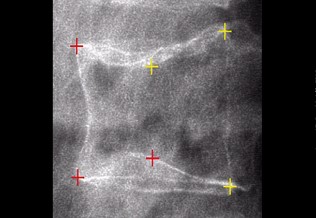

Rhumatologie

Gonalgies